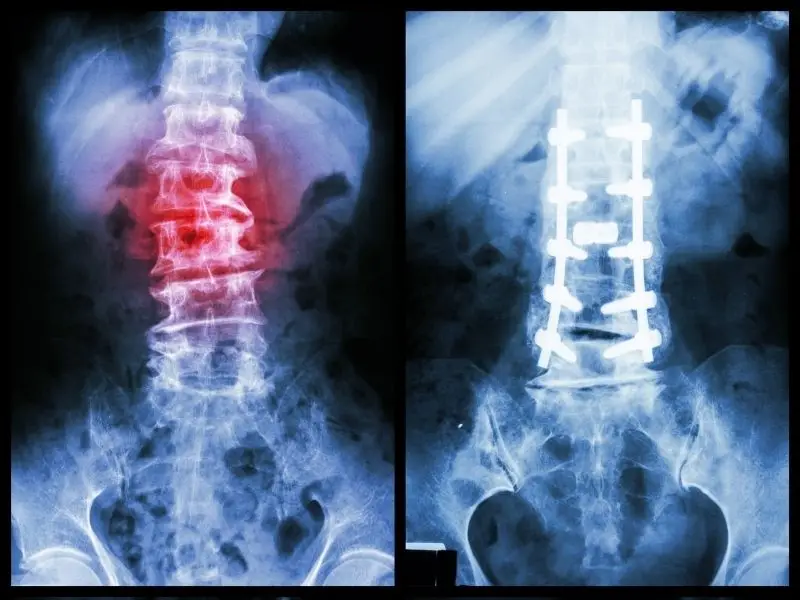

Physiotherapy is usually the first point of call for spondylolisthesis management with best results achieved when care is coordinated between the GP, physiotherapist, and exercise physiologist. In case of poor response to physiotherapy and first-line pain management in the 6-12 months, the patients are subsequently referred for more invasive treatment such as cortisone injections, nerve blocks and surgical interventions that include a varying combination of decompression, fusion and fixation of the affected segment.